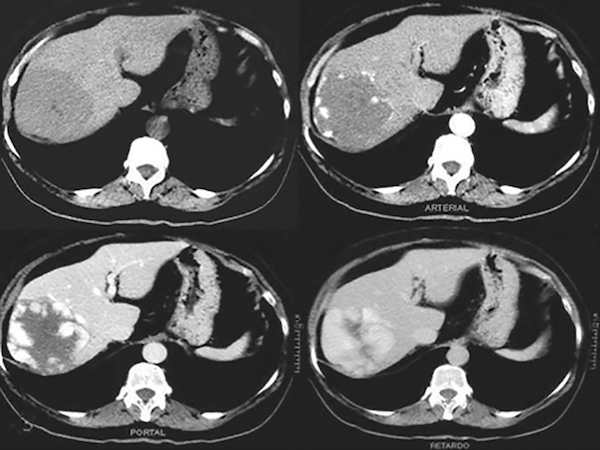

A 50-year-old woman with metastatic breast carcinoma on therapy with trastuzumab emtansine was noted to have elevated serum aminotransferases that progressively increased to twice the upper limit of normal, with associated thrombocytopenia of 146 k/µL, but she was otherwise asymptomatic. An abdominal CT scan showed signs of portal hypertension such as splenomegaly and collateral circulation without evidence of ascites or metastatic disease. Serologies for acute and chronic viral hepatitis were negative. Autoimmune serologies were positive for antinuclear antibody (1:320) but negative for smooth muscle antibody. A percutaneous liver biopsy stained with reticulin [FIGURE] showed compression of hepatic plates (arrows) alternating with thickened plates (asterisk), which suggested atrophy and regeneration, respectively. What is the most likely cause of this condition?

Nodular regenerative hyperplasia (NRH) is a rare nonmalignant liver condition characterized by the transformation of the hepatic parenchyma into small regenerative nodules, resulting in portal hypertension due to hemodynamic disturbances at the level of the hepatic microvasculature. In contrast to cirrhosis, the nodularity in NRH occurs in the absence of fibrous septa. The disease is usually asymptomatic and attracts attention only when the manifestations of portal hypertension such as ascites or variceal bleeding occur or when portosystemic collaterals are noticed on imaging studies. The prognosis is almost always related to complications of portal hypertension. Accurate NRH diagnosis is made by histopathology, which demonstrates nodules of hyperplastic hepatocytes distributed throughout the liver in the absence of fibrous septa. Histological NRH features may be incomplete or at times lacking on small liver biopsy cores and require a very high index of suspicion combined with clinical and pathological acumen for an accurate diagnosis.

This patient developed NRH during treatment with trastuzumab emtansine. Histology did not show any bile duct damage, or inflammatory cell infiltrates consistent with autoimmune hepatitis. Hepatic SOS, previously termed “hepatic veno-occlusive disease,” is characterized by hepatomegaly, right upper quadrant pain, jaundice, and ascites. Although commonly encountered in patients after hematopoietic cell transplantation, it can also occur following ingestion of pyrrolizidine alkaloids through consumption of herbal teas, after high-dose external beam radiation or radioembolization of liver tumors, and rarely after liver transplantation. Histologically, it is characterized by sinusoidal fibrosis, necrosis of pericentral hepatocytes, and narrowing with eventual fibrosis of central veins. The biopsy does not show typical features of drug-induced autoimmune hepatitis or vanishing bile duct syndrome.